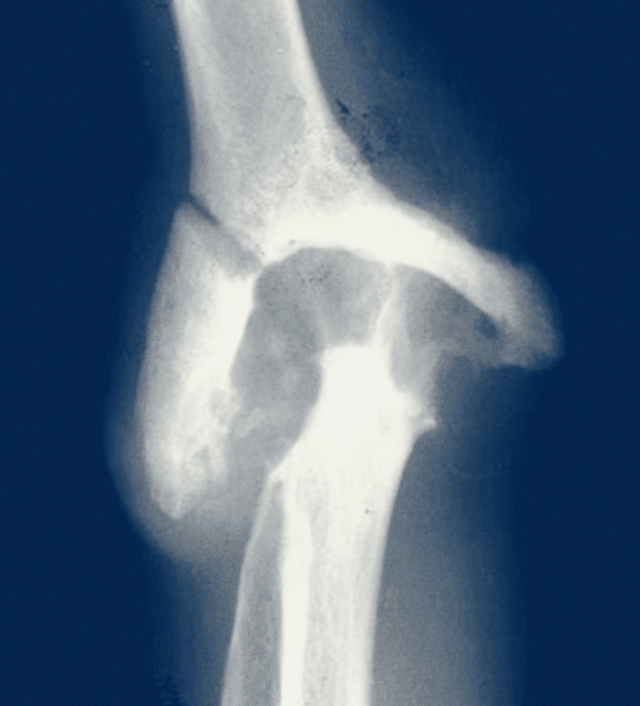

如果患者存在了症状,到医院就诊的时候,医生会给患者进行肘关节的x线检查,明确是否有大量的骨质增生,影响了患者的旋转或者是屈伸功能,另外如果患者出现了手部的麻木或者是手指的肌肉萎缩,要给予进行肌电图检查,明确肌肉的神经传导是否存在问题,到底是在神经控制的哪一个节段出现了问题。